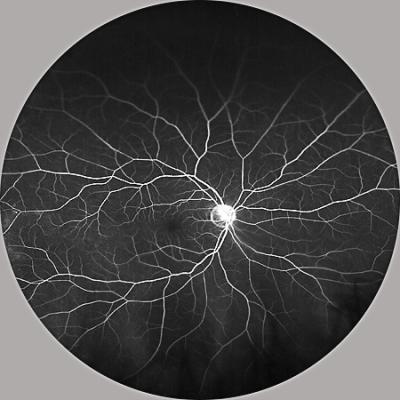

Image of the retina. Credit: Akrit Sodhi, Johns Hopkins Medicine